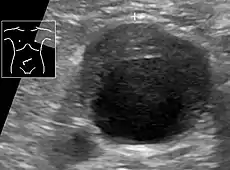

Abdominal aortic aneurysms (3.4 cm)

An aortic aneurysm as seen on CT with a small area of remaining blood flow- Ultrasound showing a previously repaired AAA that is leaking with flow around the graft[34]

Ultrasonography of an aneurysm with a mural thrombus.